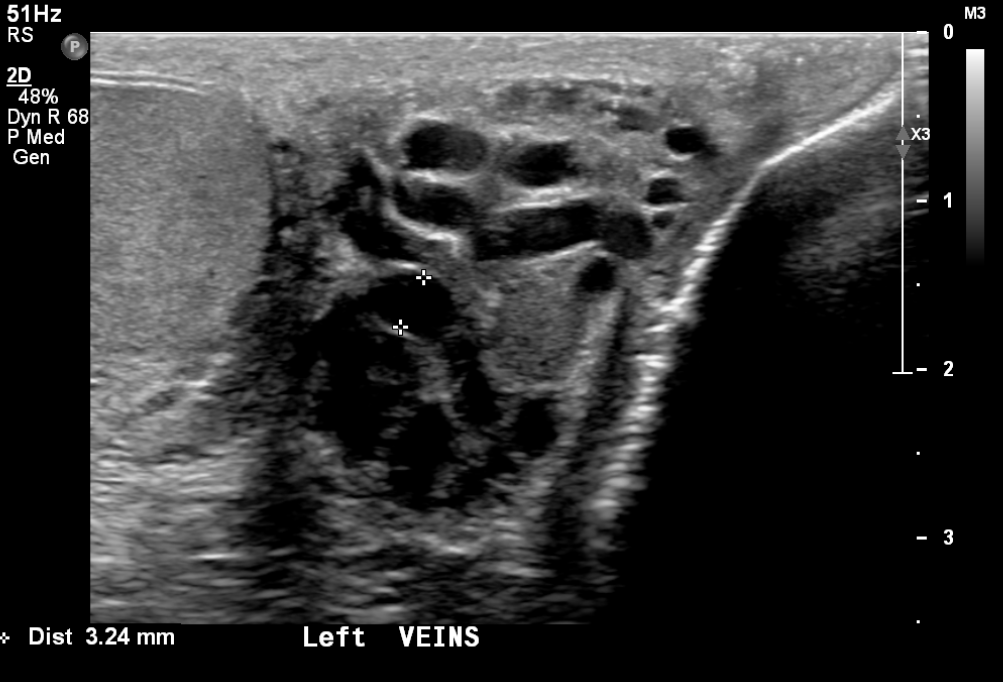

Varicocele

Varicocele Embolisation